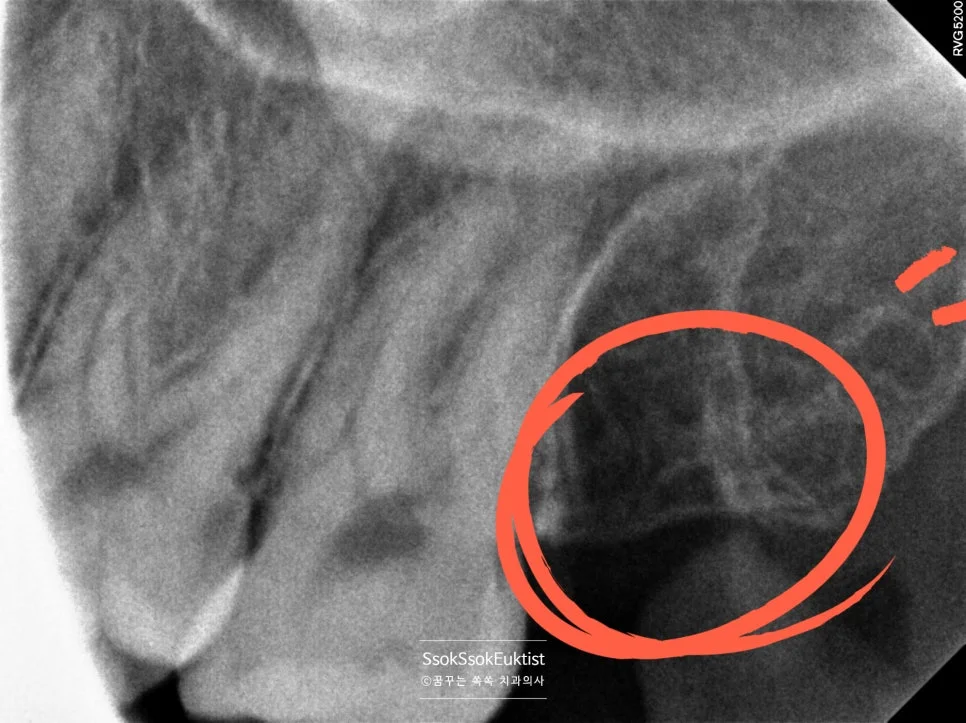

2. 한편 통증이 없더라도 매복 사랑니는 언젠가는 바로 앞어금니에 충치를 만들고, 잇몸뼈까지 잃게 합니다.

이렇게 사랑니 때문에 생긴 바로 앞 제2대구치의 충치는 치료가 매우 어렵고, 그로 인해 어금니를 뽑아야 하는 상황이 올 수 있습니다.

왼쪽 아래 매복 사랑니 발치 후 방사선

왼쪽 아래 매복 사랑니 발치 후 X-ray